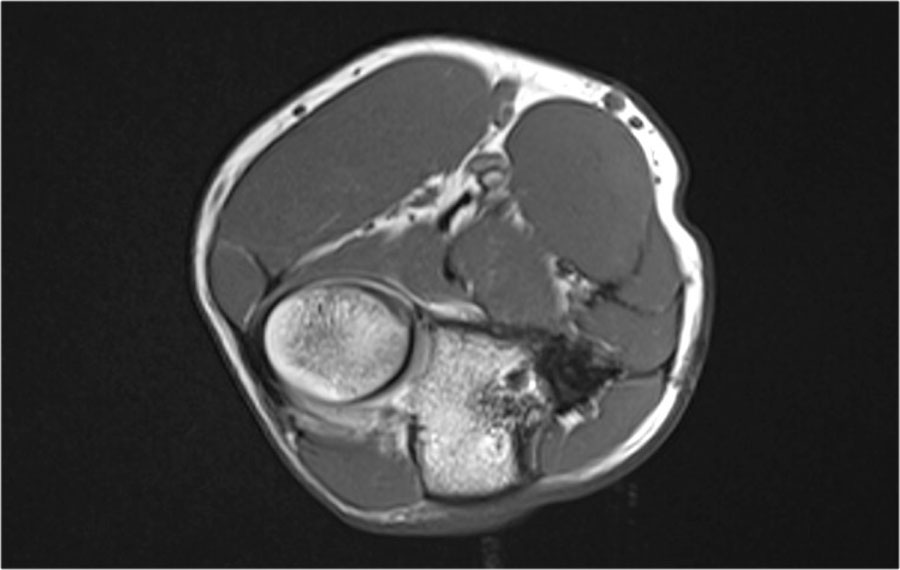

Trên các hình ảnh mặt phẳng coronal, bó trước của dây chằng UCL hiện rõ đẹp, nhưng lưu ý rằng có sự hình thành gai xương ở phần trong của khớp (mũi tên đỏ).

Khi chúng ta đi xa hơn về phía sau có một vùng nhỏ có tín hiệu thấp (mũi tên vàng), đây là một chỗ bong gân của một phần dây chằng bên trụ (UCL).

Điều này được thể hiện rõ hơn trên phim X-quang.

Continue with the axial scan.

Khi quan sát trên lát cắt ngang (axial), chúng ta có thể nhận thấy sự hình thành gai xương khổng lồ.

Lưu ý rằng dây thần kinh trụ (mũi tên màu xanh) nằm cạnh các gai xương này và những bệnh nhân này có thể biểu hiện bệnh lý thần kinh trụ.